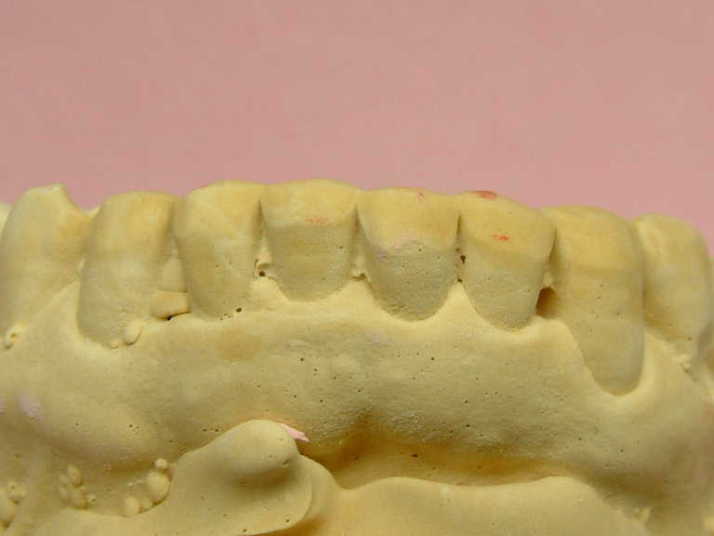

補綴物物 完成

患者さんから「出っ歯にならないよに!」

と再度念を押されたので

出来る限り内側に入れて製作しました。

模型上では、1.1下部孤形空隙が広いように

見えますが、歯肉模型にて調整して

歯肉を圧迫せず、息が漏れることが無いように

調整しました |